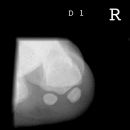

Sprinteraufn. Sesambein D1 tangential

Auf Höhe des Caput metatarsale I im senkrechten Strahlengang tangential zur Plantarfläche.

enge Einblendung nur über die Sesambein

Überlagerungsfreie Darstellung der Sesambeine und der Mittelfußköpfchen.